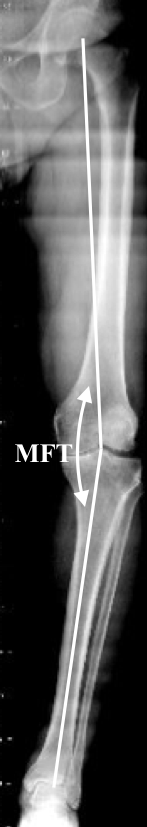

Considering these definitions, overall alignment can be described in two ways, using either the anatomical femoral-tibial (AFT) angle or the mechanical femoral-tibial (MFT) angle. The AFT angle is simply the angle between the anatomical axis of the distal femur and the anatomical axis of the proximal tibia. In a normal knee the AFT should be about 6° of valgus (range 4 to 9°). The MFT represents the angle between the mechanical axis of the femur (centre femoral head and centre distal femur) and mechanical axis of the tibia (centre proximal tibia and centre ankle). In a normal knee the MFT should be neutral 0° (range 3° valgus to 3° varus). While the AFT angle can be estimated from standard (short-leg) radiographs, measurement of the MFT angle requires long-leg radiographs (Figure 3). The AFT does not represent the real lower limb alignment and allows pure guessing of the mechanical axis of the lower limb.